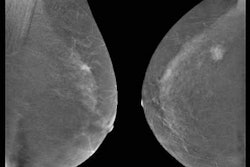

Contrast-enhanced mammography exam of both breasts in two views. In the first two low-energy images (A, B), an ill-defined mass can be seen in the upper outer quadrant of the right breast at the location of a palpable mass in a 52-year-old patient. In the left breast, no relevant abnormalities can be detected. In the recombined images (C, D) of a contrast-enhanced mammography examination, contrast uptake can be appreciated. The recombined images show an irregular enhancing mass in both breasts -- both in the upper outer quadrant. Tissue sampling revealed a bilateral invasive breast cancer of no special type. A breast MRI examination performed prior to surgery also confirmed the presence of two irregular enhancing masses on these contrast-enhanced T1 weighted images (E: top example is the cancer in the right breast; bottom example is the left breast). All images courtesy of Dr. Marc Lobbes, PhD.